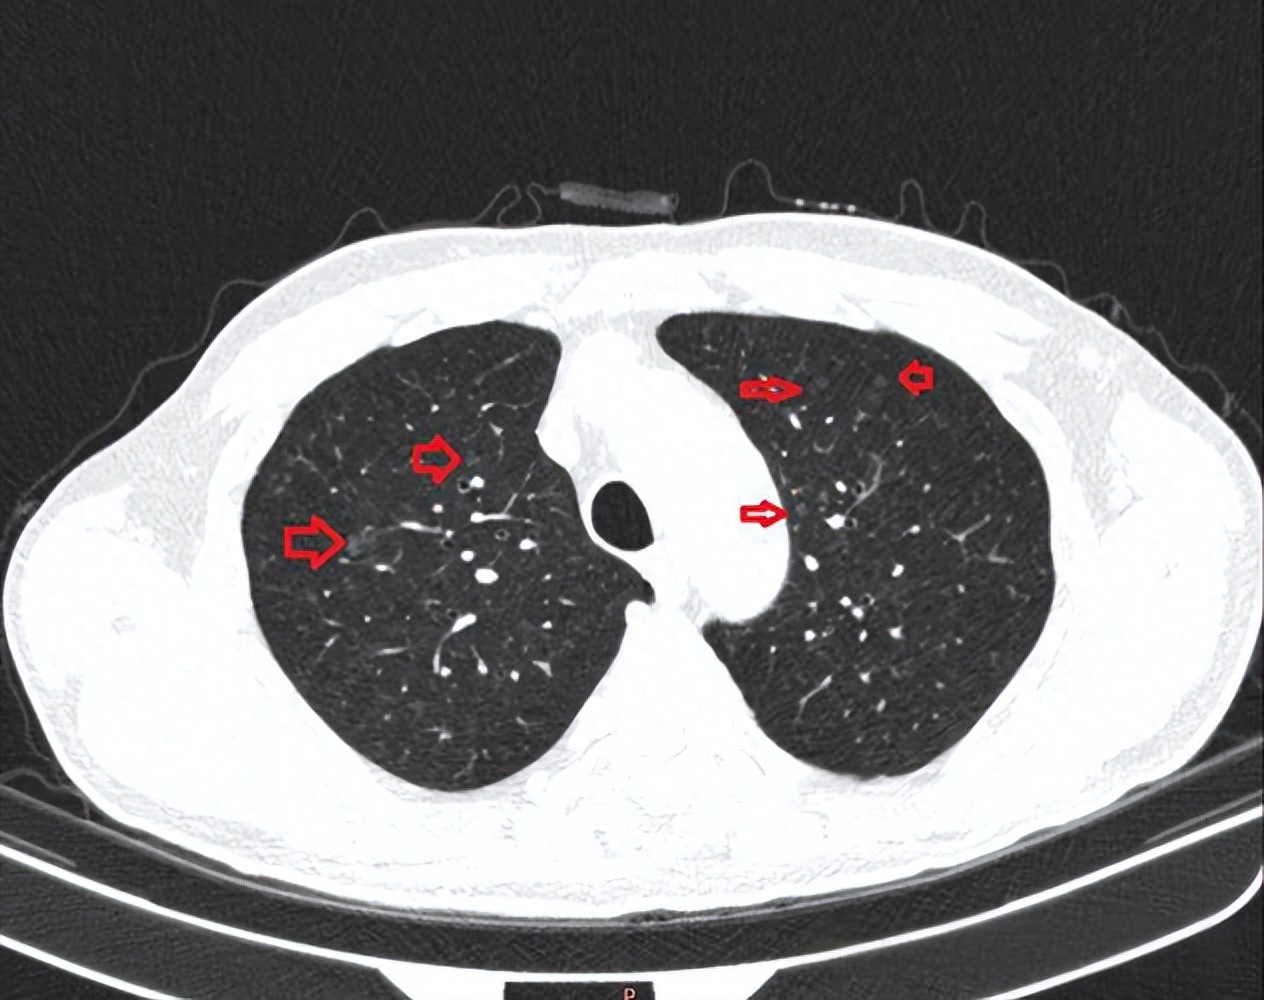

A lung nodule is an imaging finding, often discovered during physical examinations or other disease screenings. There are numerous causes of lung nodules, which may be due to conditions such as lung infections, tuberculosis, benign lung tumors, or lung cancer.